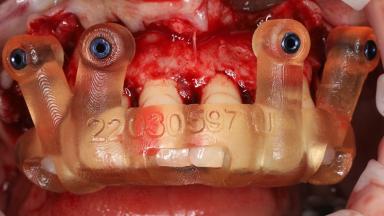

In this video Dr. Legg will demonstrate the process of utilising fully guided surgery as well as reconstruction to provide immediate full arch rehabilitation. A 56-year-old female with chronic adult periodontitis had previously undergone significant nonsurgical periodontal therapy. Unfortunately she had reached the stage where she was no longer happy with the appearance of her teeth and was suffering from increasing discomfort. A full workup was carried out in conjunction with a technical design team (at Createch). This included digital wax up of the proposed teeth, digital placement of the proposed implants and the design of the requisite surgical guides. The surgery was then carried out under sedation. The remaining upper teeth were removed, bone reduced where appropriate and the implants placed using a fully guided protocol. Following placement of screw retained abutments, the immediate provisional prosthesis was picked up in situ and passed to the technician for finishing before being fitted.